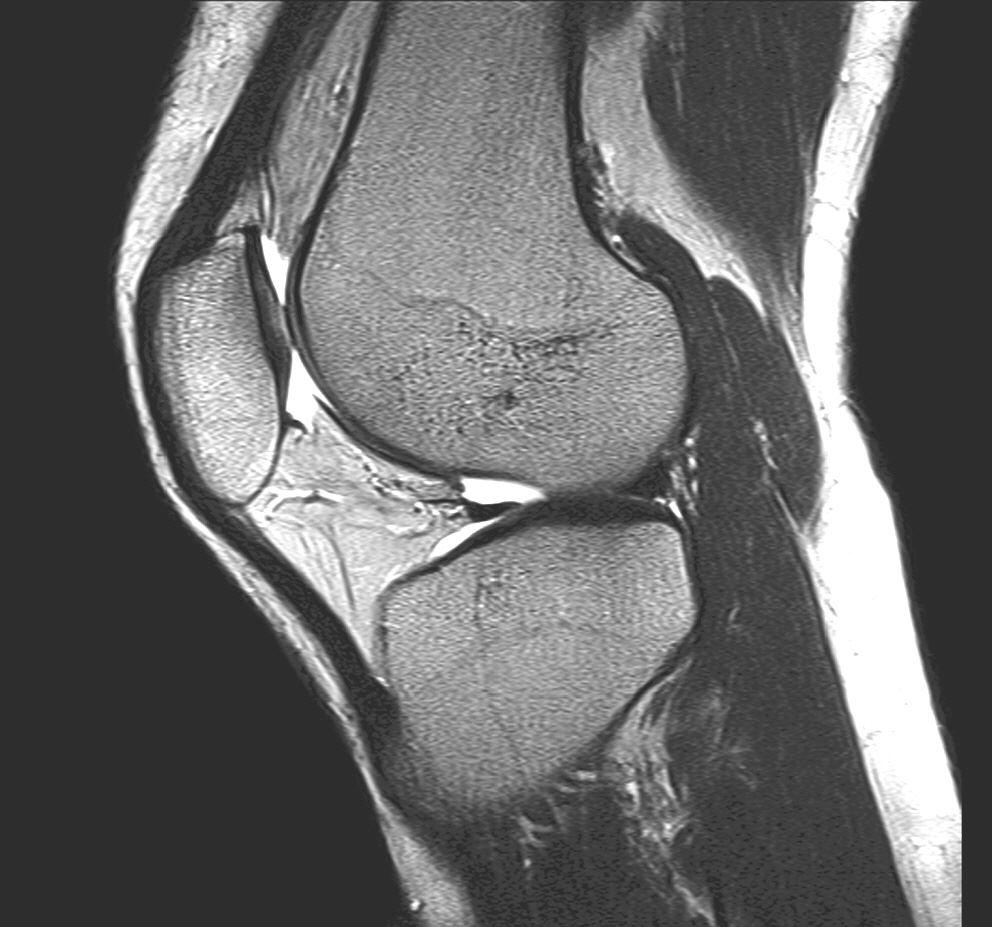

Die MRT ist inzwischen unverzichtbarer Bestandteil der Diagnostik am Bewegungsapparat. Muskeln, Sehnen, Bänder, Knochen und Knorpel, sowie deren Krankheitszustände lassen sich in unvergleichlicher Weise differenzieren. Einige Krankheitsbilder wie z.B. das "traumatische Knochenödem" oder die knöcherne Stressreaktion sind überhaupt erst durch die MRT bekannt geworden.